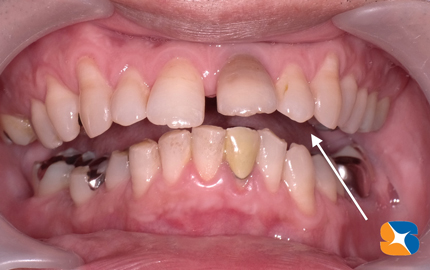

60代の超・怖がり(歯科恐怖症)の女性。これは、当院で7年前に治療を終えた時の写真。本日の主訴は「右下の歯茎が腫れてきて、入れ歯が痛くて入らない。」でした。

健康な時の歯茎の様子